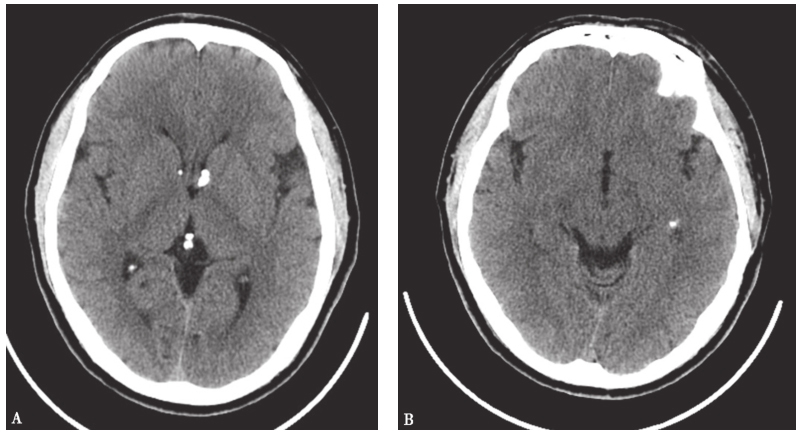

因患者临床表现与该病理诊断不完全符合,故当时未行抗肿瘤治疗,继续随诊观察。半年后,患者额部、背部皮疹较前明显,呈血管纤维瘤表现(图17),头颅CT可见多发室管膜下钙化、皮质钙化(图18)。再次病理会诊,肺部病变诊断为多灶微结节性肺泡上皮增生。

图18头颅CT表现

最后诊断:多灶微结节性肺泡上皮增生、结节性硬化症。